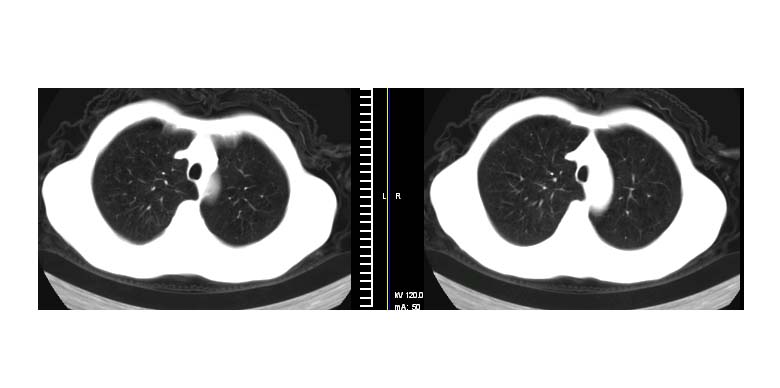

标题: CT11019:男性,66岁。发烧5-6天。治疗后无明显好转。 [打印本页]

标题: CT11019:男性,66岁。发烧5-6天。治疗后无明显好转。

考虑左肺下叶肺炎建议抗炎治疗后复查.

阻塞性肺炎并不张,建议抗炎治疗后复查或增强

考虑左肺下叶炎症合并叶间裂积液,建议抗炎治疗后复查

左下肺实变,考虑炎症

左肺下叶炎症不除外 建议抗炎治疗后复查

节段性肺炎可能,建议系统的,正规的抗炎后复查。以排除占位。